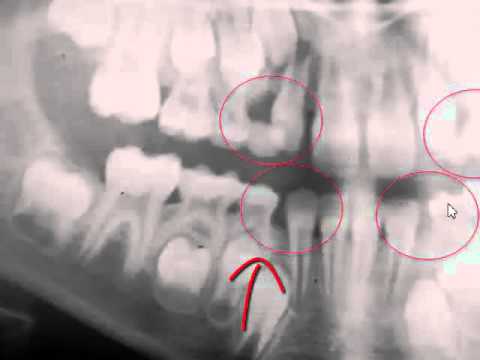

INTERCEPTIVE ORTHODONTICS :Extractions Guidelines of First Parmanent Molars.

INTERCEPTIVE ORTHODONTICS Extractions Guidelines of First Parmanent Molars